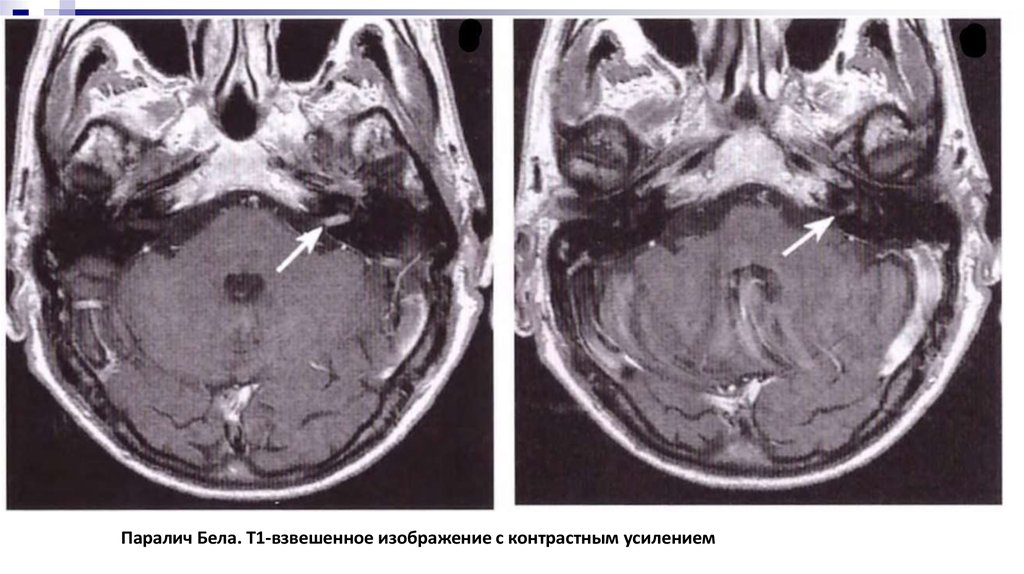

Паралич Бела. T1-взвешенное изображение с контрастным усилением